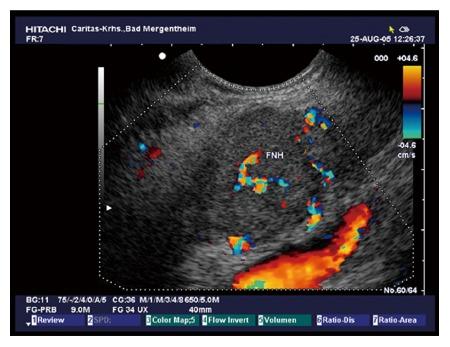

Female predominance is seen with most SPNs presenting asymptomatically in the 5 through 7 decade. Mean lesion size was 38.7 mm, 98% were single, 44.2% cystic, 46% mixed cystic and solid, and 94% hypoechoic on B-mode ultrasound. Vascular patterns and contrast-enhancement profiles are described as hypervascular and hyperenhancing.

大多数 SPN 以女性为主,无症状表现,发病年龄在 5 至 7 十年代。平均病变大小为 38.7 毫米,98%为单发,44.2%为囊性,46%为囊实性混合,94%在 B 模式超声下呈低回声。描述了血管模式和对比增强特征为富血管性和高增强性。